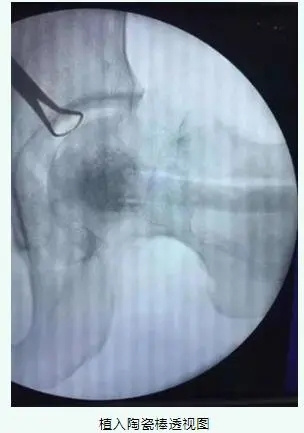

這種微創(chuàng)保髖手術(shù)是通過(guò)特殊的手術(shù)器械來(lái)完成,傷口長(zhǎng)約1.5cm,手術(shù)過(guò)程在C臂機(jī)透視下完成,不需要打開(kāi)關(guān)節(jié)腔暴露髖關(guān)節(jié),因而關(guān)節(jié)感染等風(fēng)險(xiǎn)大大降低,利用特殊器械清理完壞死區(qū)后就可以進(jìn)行自體骨粒植骨,并且使用生物陶瓷棒進(jìn)行支撐。

生物陶瓷棒微創(chuàng)治療是一種全新的治療理念。專(zhuān)用的“潛行刮刀”,能夠準(zhǔn)確有效地清除壞死骨組織,為骨重建創(chuàng)造空間;并能很好地實(shí)現(xiàn)骨內(nèi)減壓,由于術(shù)中的徹底骨內(nèi)減壓,能顯著有效地消除骨內(nèi)高壓引起的疼痛。準(zhǔn)確有效地清除死骨,為修復(fù)提供空間;陶瓷棒植入能將粗隆和頸部的優(yōu)良血循環(huán)引導(dǎo)至頭部,最終達(dá)到股骨頭血循環(huán)重建和復(fù)活。

術(shù)后影像